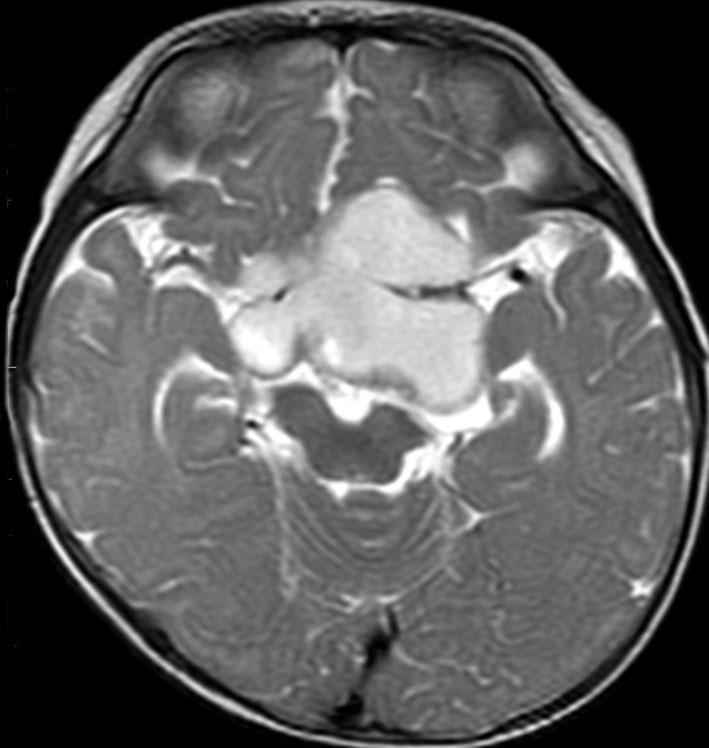

whole optic pathway pilocytic astrocytomaとは

両側の眼窩内視神経から視交叉、視索,外側膝状体,内包後脚,視放線近位部までが腫瘍化しています。FLAIRで高信号で,不規則にガドリニウム増強されます。これを手術摘出したり生検したりしても無駄です。放射線治療は不可能であり治療方法は化学療法のみです。

この子はCDDP/VCRの化学療法から開始して12年になりますが,今は無治療でわずかな視力ですが学校に通っています。優等生です。自然退縮を見ていますが,今後も変化する可能性はすこし残しています。